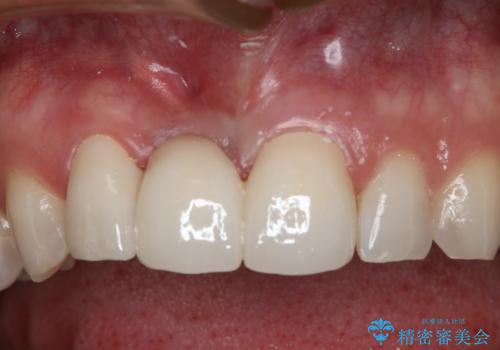

周りの歯との色調に合わせた綺麗なブリッジを入れることができました。